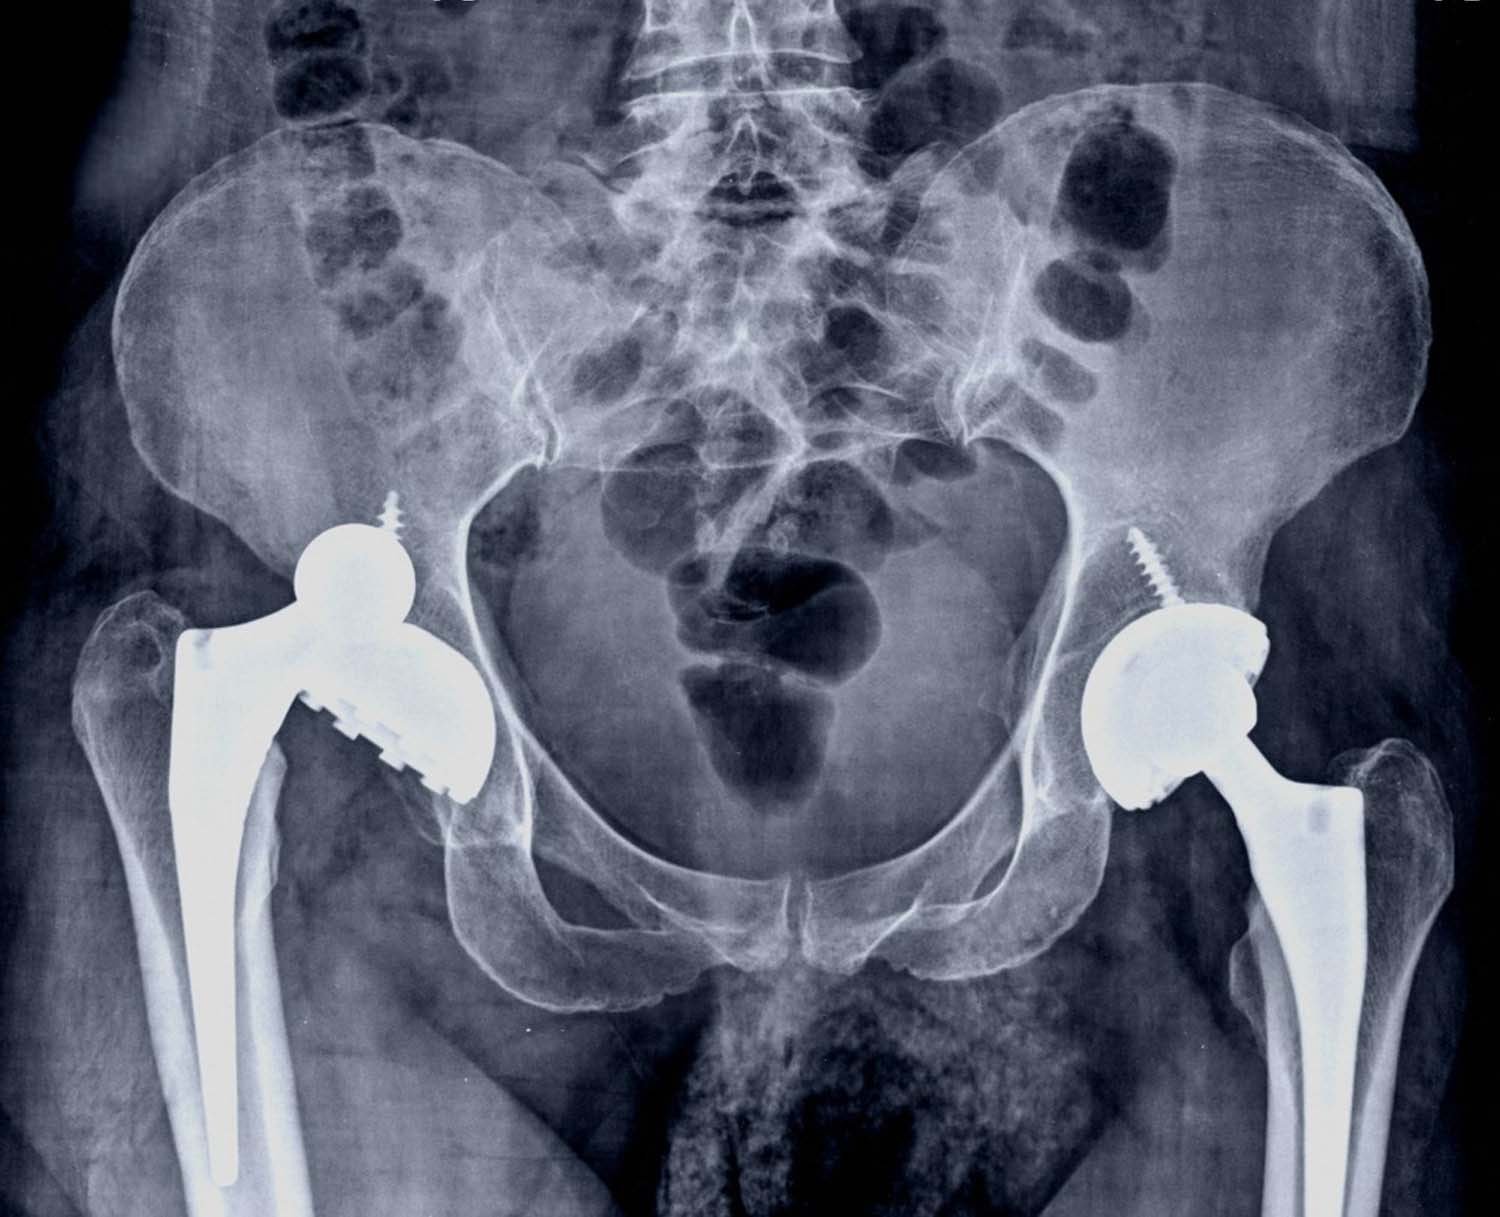

Revision hip replacement is a complex surgical procedure in which all or part of a previously implanted hip-joint is replaced with a new artificial hip-joint. Total hip replacement surgery is an option to relieve severe arthritis pain that limits your daily activities. During total hip replacement, the damaged cartilage and bone is removed from the hip joint and replaced with artificial components. At times, hip replacement implants can wear out for various reasons and may need to be replaced with the help of a surgical procedure known as revision hip replacement surgery.

Indications of Revision Hip Replacement

Revision hip replacement is advised in patients with the following conditions: